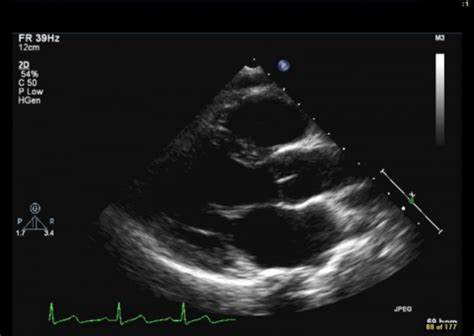

Description: Anatomy of PLAX